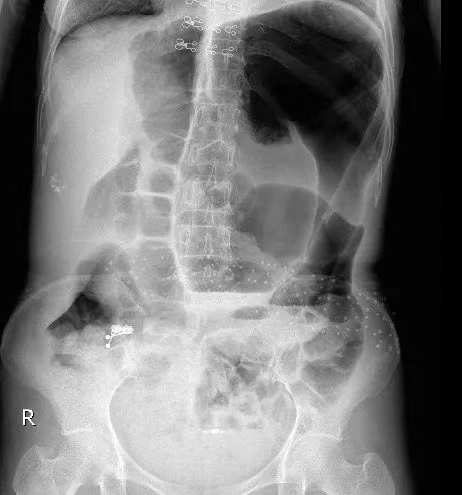

肠梗阻,简单讲是指肠道的正常运动受到阻碍,导致食物、液体和气体无法顺利通过肠道。

急性肠梗阻最常见的原因包括肠粘连、肿瘤和疝气。腹部手术病史引起的粘连是小肠梗阻的主要原因,占病例的60%至75%。继发于肿瘤的梗阻在大肠中更常见。其他原因包括炎症性肠病、肠套叠、肠扭转、胆结石和肠管异物。